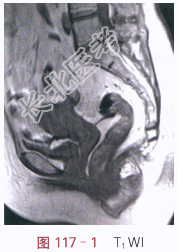

影像学资料如图117-1~图117-5所示。

读片分析:子宫稍增大,内膜弥漫性增厚,结合带中断。增强扫描后,增厚的内膜呈不规则强化,局部浸润超过肌层1/2厚度。